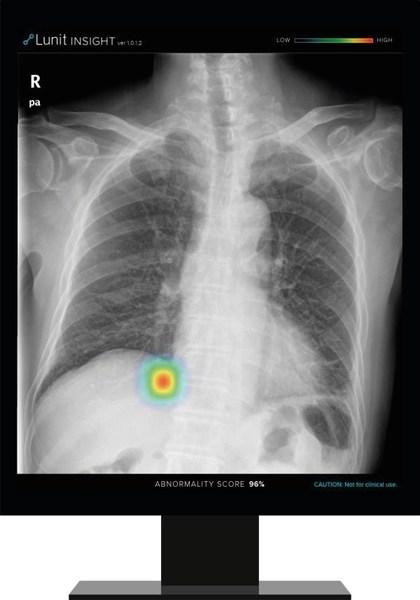

Lunit INSIGHT CXR chest detection suite accurately detects 10 of the most common findings in a chest X-ray. The announcement is the latest extension of Philips’ AI portfolio in precision diagnosis, which leverages this collaboration to achieve better patient outcomes, improve the experience of patients and staff, and lower the cost of care.

Lunit’s AI software, Lunit INSIGHT CXR, is designed to provide accurate and instant analysis of chest X-ray images by mapping the location of the findings and displaying the scored calculation of its actual existence. It accurately detects 10 of the most common findings in a chest X-ray, prioritizes cases with abnormality scores, thereby allows fast triage of normal cases and enables radiologists to focus on reading abnormal cases. The algorithm performs at 97-99% accuracy rate, with its performance validated in major publications such as Radiology, JAMA Network Open, etc.